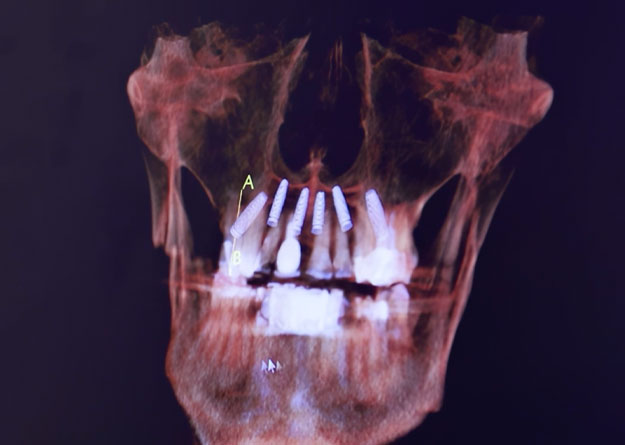

Most patients can receive their implant restorations in as few as two visits to our Scottsdale office. Our onsite 3D imaging technology also allows us to take in-depth images of your jawbone to find the best placement site and map out a treatment plan that will provide the best results.

Once the numbness sets in, Dr. Call will insert your implant directly into your jawbone. He’ll then place a temporary crown to protect your implant site while osseointegration occurs. This is the process in which your implant fixtures fuse to your jawbone for a lifelong restoration. Osseointegration typically takes four to six months to complete.